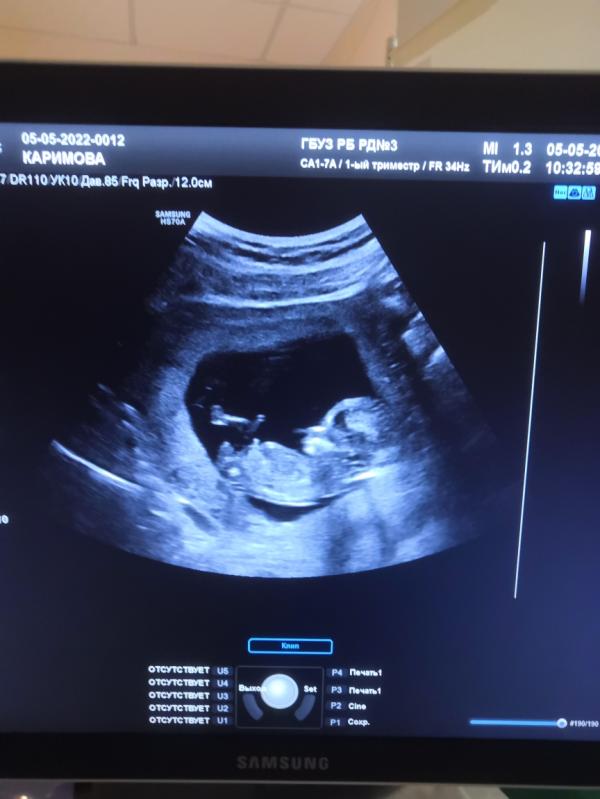

На фото 12, 6 неделек нашей или нашему крохе💋 #первыйпост

Блин вот почему у всех видно а у меня не видно кто там 😫😫😫😫 😀😀😀😀. Поздравляю, видать у всех мужиков генетикой заложено лежать и писюльку сразу проветривать и показывать😀😀😀😀

Мой так лежал кстати 😁тоже сама сразу увидела что мальчик и врач сказала

Мы тоже думаем, что мальчик! Все так говорят. Посмотри, что скажут на 2 скрининге.